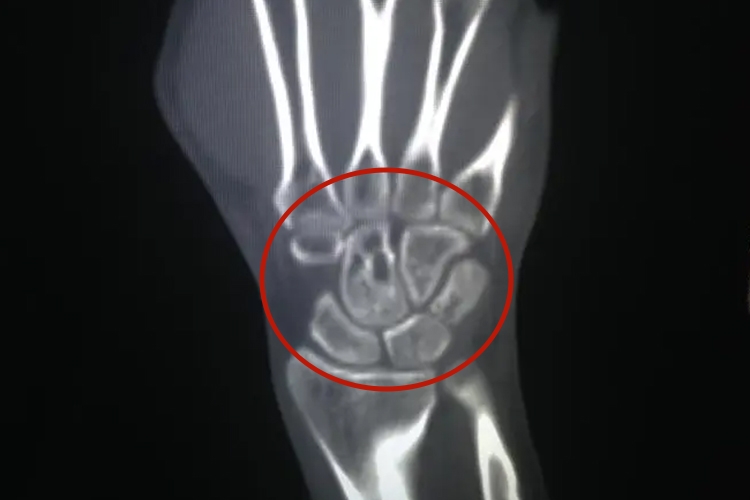

正常人手腕骨头CT显示关节面光滑,关节间隙无明显狭窄,关节腔内未见积液征象等。

正常人手腕骨头CT检查时双侧腕关节CT平扫(1个部位)和二、三维成像(1个部位)显示双侧腕关节对称,骨质未见明确异常改变,关节面光滑,关节间隙无明显狭窄,关节囊无肿胀,关节腔内未见积液征象。

当手腕骨头缺血性坏死时,如舟骨发生骨缺血性坏死时,其骨密度的改变在CT检查中易于发现。可有月骨、舟骨密度增高,尤其松质骨密度增高,中间会有低密度线状影。月骨、舟骨体积变小、变扁。骨皮质中断、消失。恢复期时,密度会逐渐恢复正常。